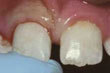

Repaired

Abgesplitterter Zahn nach Wiederherstellung